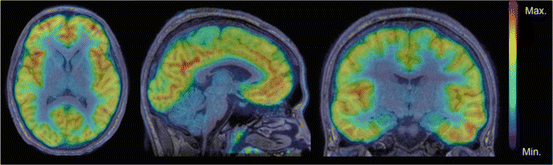

Among serotonin receptors, 5-HT2A, is the most abundant in the human cortex, especially in prefrontal and cingulate regions tied to mood and cognition. It is influenced indirectly by traditional antidepressants, acted-on directly by several add-on medications (such as second-generation antipsychotics) and all classical psychedelics act primarily on this receptor. The presence and density of these receptors can be quantified in living humans with brain imaging using established radiotracers, and a number of research trials have investigated it in the past, with some mixed results. (In case you are wondering, the 2022 Moncrieff et al. umbrella review did not look at 5-HT2A.)

Authors of the present paper reviewed and combined evidence from brain-imaging studies (PET and SPECT) and post-mortem radioligand studies that measure how strongly tracers bind to cortical 5-HT2A serotonin receptors (5-HT2ARs) in people with major depression and in individuals who died by suicide. From each study, they extracted receptor-binding data and pooled results using random-effects meta-analysis. 31 studies contributed data from 556 people with major depression or who died by suicide and 526 healthy controls. They focused on patients who were unmedicated at the time of the study, from at least one week to never having taken them.

In living MDD patients who were actively depressed and were off antidepressants at the time of the study, cortical 5-HT2A receptor binding was lower than in controls in several brain areas (frontal, prefrontal, cingulate, anterior cingulate cortex, and temporal cortex). The associations were generally of a medium size (effect sizes ranged from g = –0.40 to –0.57).